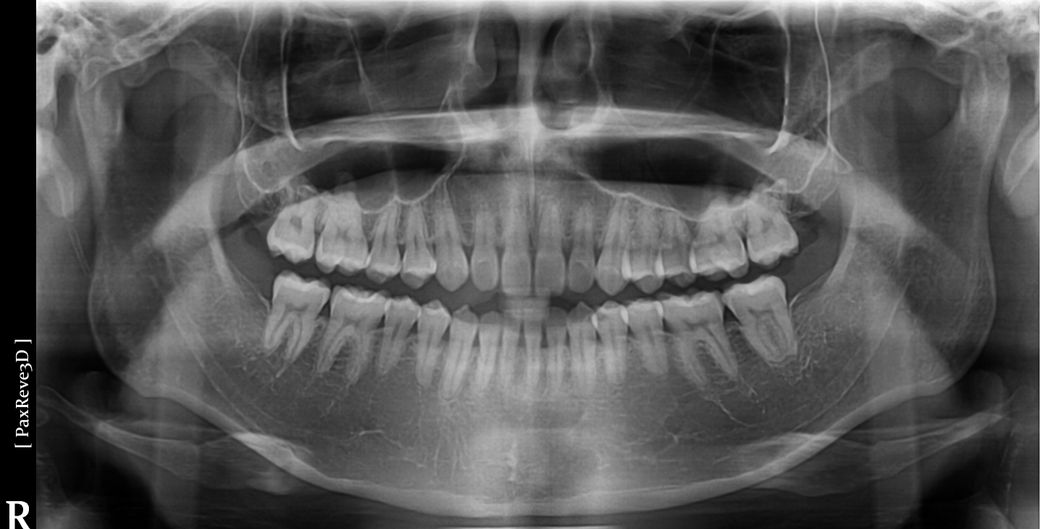

질문4. 제가 가끔 오른쪽 턱관절이 따닥소리나고 통증이 있을때가 있는데 파노라마 사진보면 관절구나 전체적인 턱 상태가 정상일까요?

• 3번 째 사진

4. 현재 상태에서는 정확한 턱관절 상황을 알 수 없으나 사진 상으로 보아서는 크게 문제가 되는 부분은 없습니다. 물론 정확한 판단을 위해서는 ct 및 방사선 뷰가 필요합니다.

-턱관절에 통증이 잇거나 소리가 난다면 턱관절에 문제가 있을수 잇습니다. 통증이 지속되거나 증가된다면 턱관절 검사를 받아보시는게 좋을것같습니다.